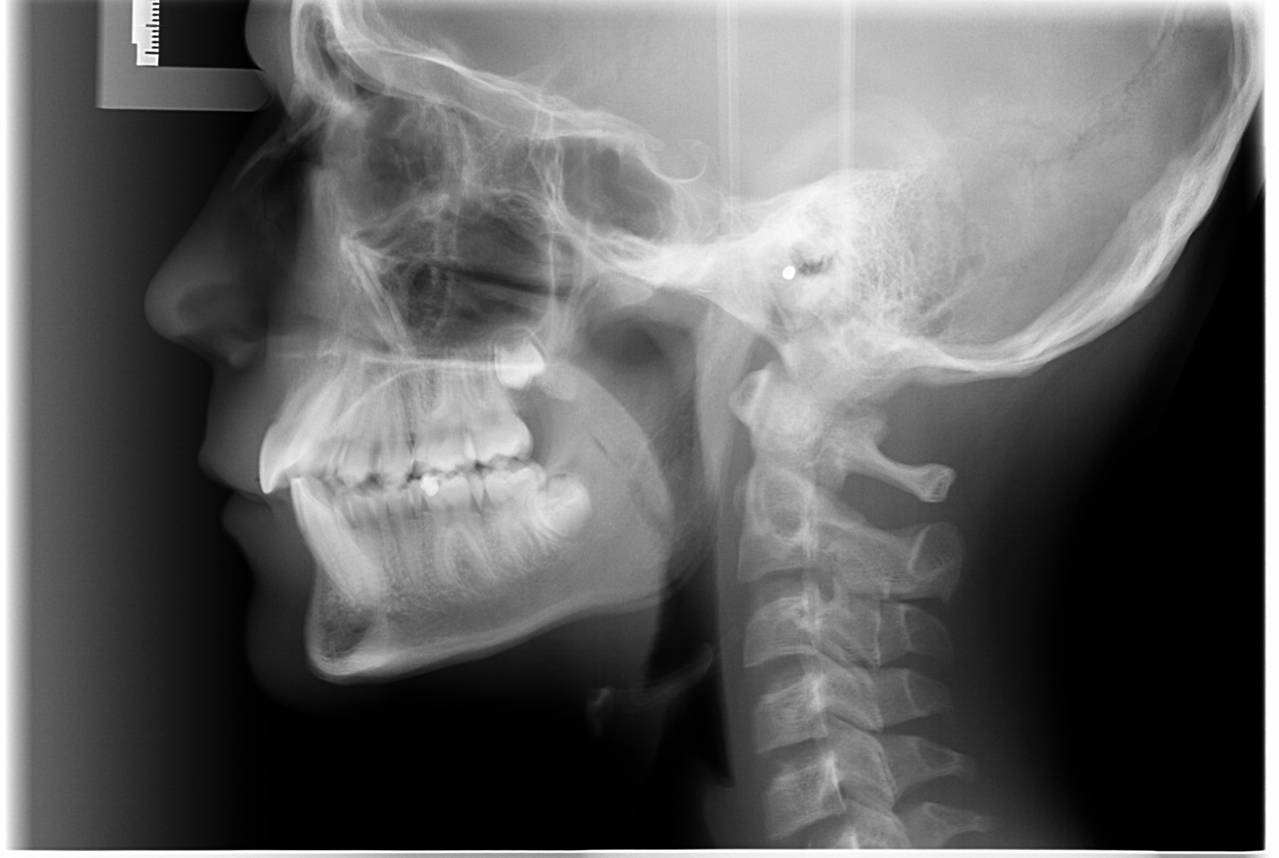

- Vi tager røntgenbilleder af tænder, kæber og hoved.

Når du har takket ja til tandreguleringsbehandling, har du og dine forældre også givet accept til, at vi tager et røntgenbillede ca. hver 6. måned.

Vi tager røntgenbilleder for at kontrollere, om rødderne kan klare belastningen med faste bøjler.